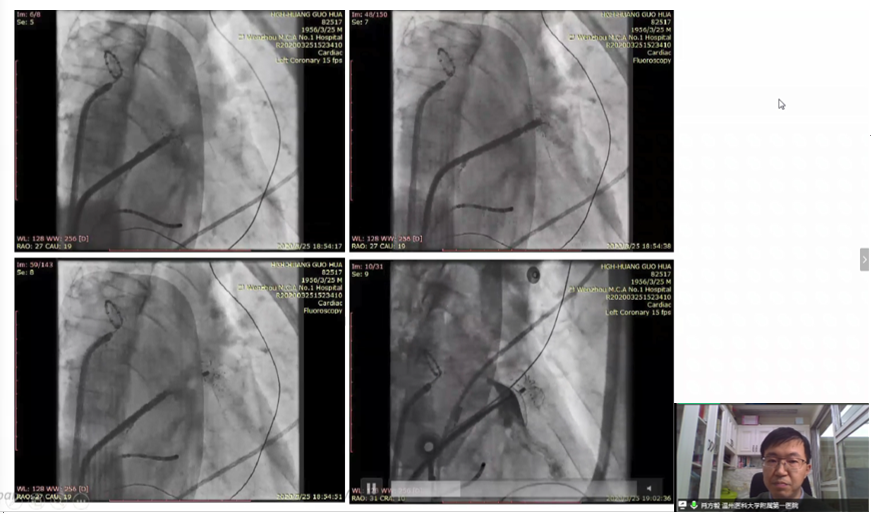

病例讨论环节中,温州医科大学附属第一医院肖方毅教授通过一例双分叶大开口心耳病例分享了“渐进式”释放技巧。术中,肖方毅教授选用型号为LT-LAA-2436的小伞大盘型LAmbre™左心耳封堵器,并灵活运用“渐进式”释放技巧,获得了满意的封堵效果。“渐进式”释放技巧能够确保固定盘上8个U型钩充分打开,更利于完成高质量的C(Circumflex artery)O(Open fully)S(Sealing)T(Tug test),减少心包积液的风险。

《双分叶大开口左心耳封堵一例》--肖方毅教授